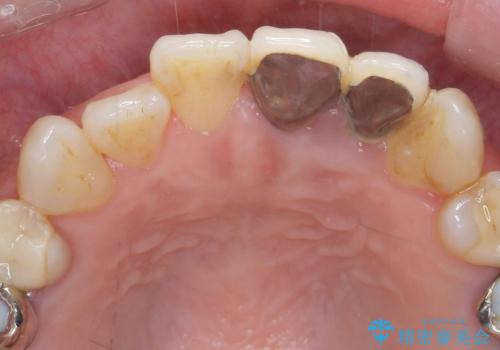

X線撮影や歯周組織検査から、クラウン下の虫歯の再発や歯の破折が疑われる状況でした。

左上2は、クラウン メタルコアの除去を行ったところ虫歯の再発や亀裂を認め、長期的な予後の期待が難しいことから抜歯を行い

ブリッジで審美性の回復を行っていく運びとなりました。